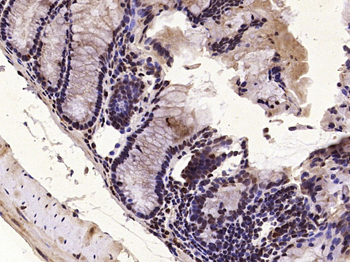

MKP1 Rabbit Polyclonal Antibody

DUSP1

KLH conjugated synthetic peptide derived from human DUSP1 (151-250/367aa)

免疫原:KLH conjugated synthetic peptide derived from human DUSP1 (151-250/367aa)

预测反应性:Bovine, Canine, Equine, Mouse, Rabbit, Rat, Sheep

应用稀释比例:WB=1:500-2000